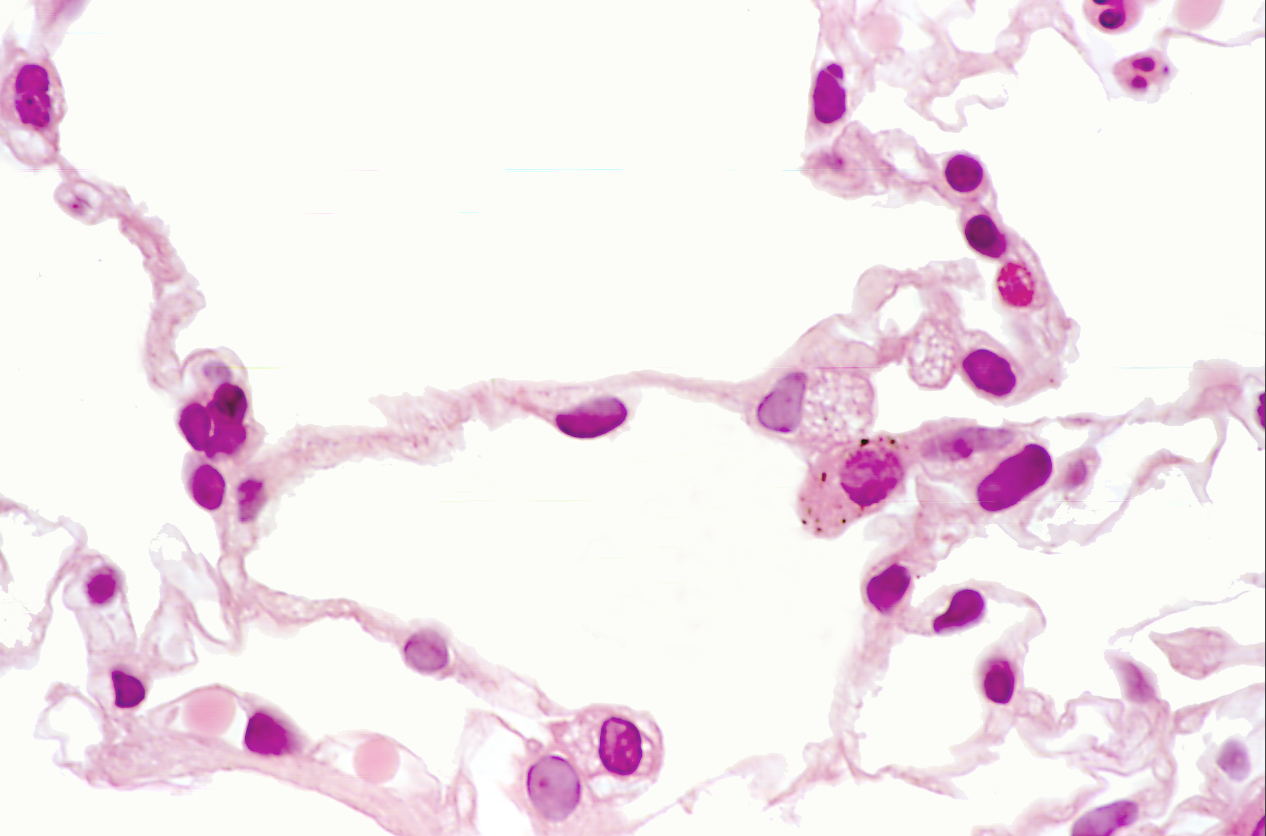

Lung tissue

NOTICE: THE OPEN SPACE OF THE ALVEOLI

Lung